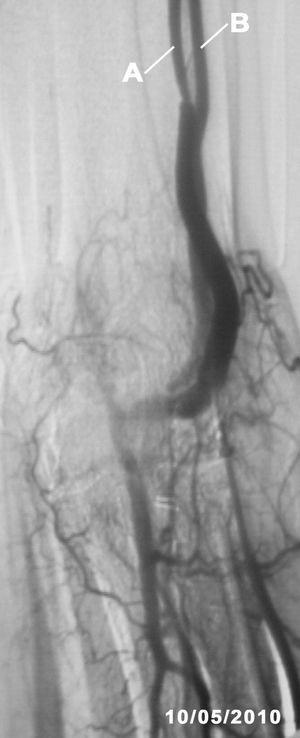

The fistulography (Figure 2) confirmed the ultrasound findings, a haemodynamically significant (80%) stenosis at 10cm from the arteriovenous fistula and another smaller one in the proximal third of the cephalic vein. Percutaneous angioplasty was performed on the 2 stenoses with good angiographic results. The identified collateral vessel was not treated in any way.

Figure 2. Fistulography image taken after percutaneous angioplasty to both stenoses